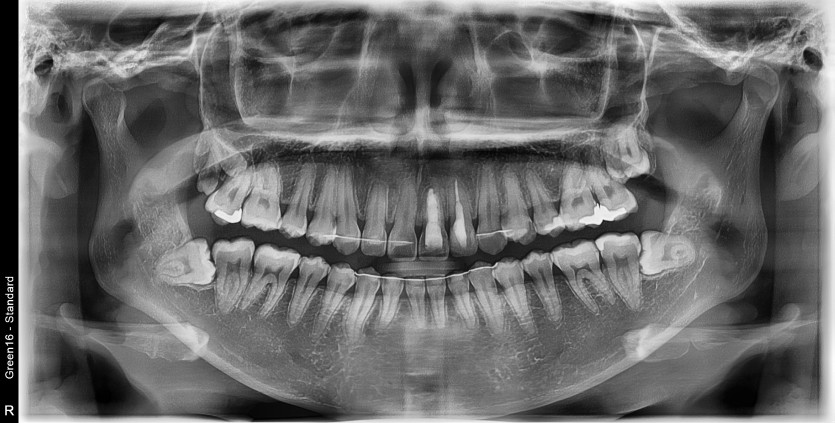

#28,38 사랑니 발치

구강 외과 전문의가 당일 발치했습니다.